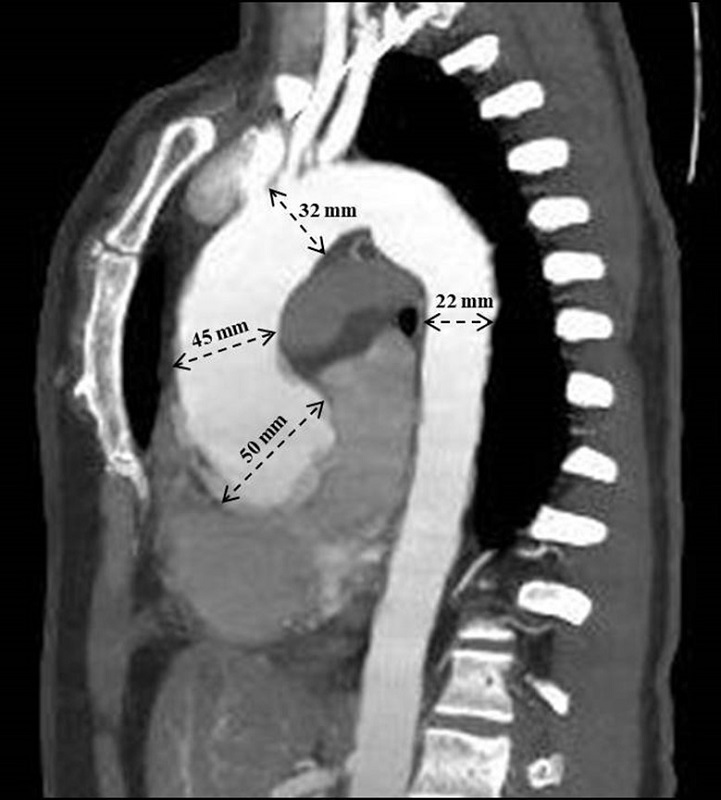

On angiotomography, the aortic root measured 50 mm (Figure 1), the ascending segment 45 mm, the aortic arch 32 mm, the descending segment 22 mm, and the abdominal segment 17 mm. Surgery for aortic aneurysm correction was indicated. A coronary angiography was requested in the preoperative evaluation, excluding coronary obstructions.